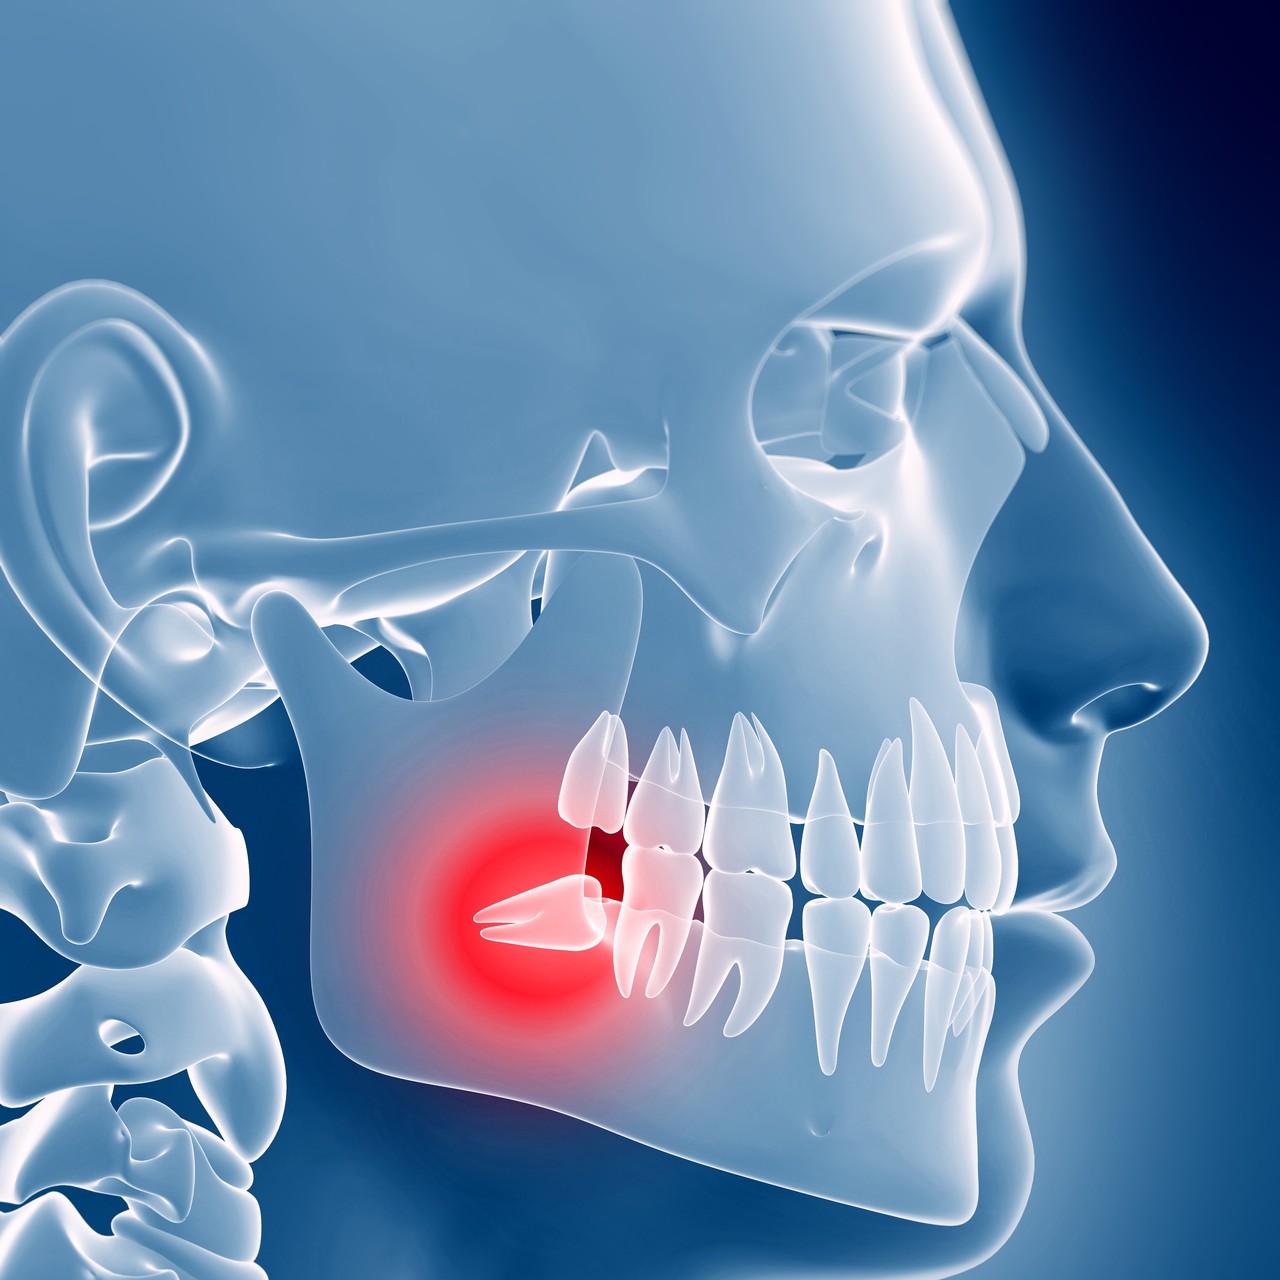

사랑니발치,

구강 건강을 지키는

예방길입니다.

사랑니발치는

경험 많은 의료진을 만나는 것이 가장 중합니다.

주변 치아나 신경에 영향을 주지 않는 안전한 발치,

연세토브치과에서 경험하실 수 있습니다.

• 사랑니 발치를 미루면 안 되는 이유?

> 구강 관리가 어려워 충치 또는 잇몸 질환 발생

> 사랑니는 물론, 다른 치아까지 충치 감염 가능성

> 위상 상태 저하로 구취 및 염증 발생

> 사랑니가 제자리를 잡지 못해 치열 틀어짐

구강 건강을 지키는 예방길입니다.

사랑니발치는 경험 많은 의료진을 만나는 것이 가장 중요합니다.